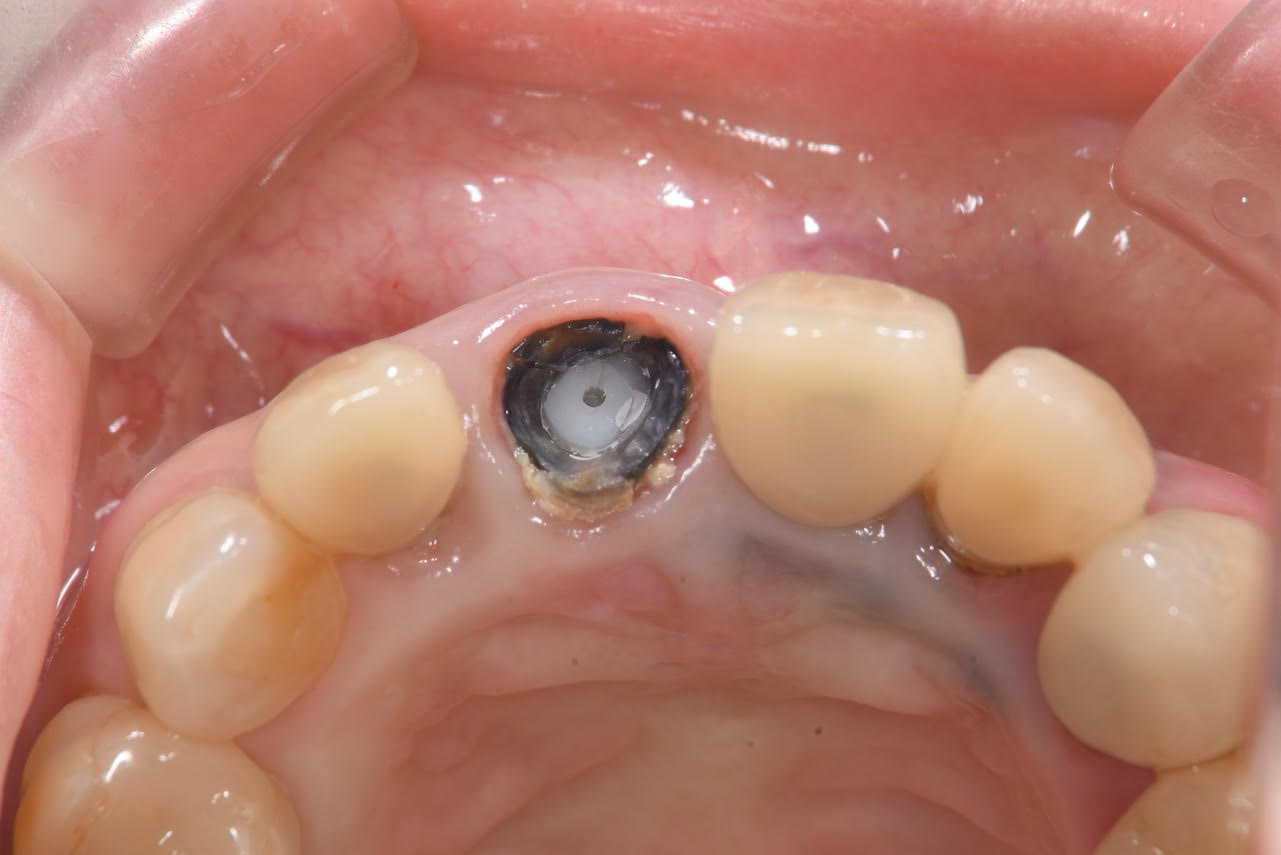

術後3ヶ月の治癒期間を経て、インプラントと骨が強固に結合していることを確認しました。

その後、最終的な上部構造(セラミックの被せ物)の型取りを行い、装着いたしました。